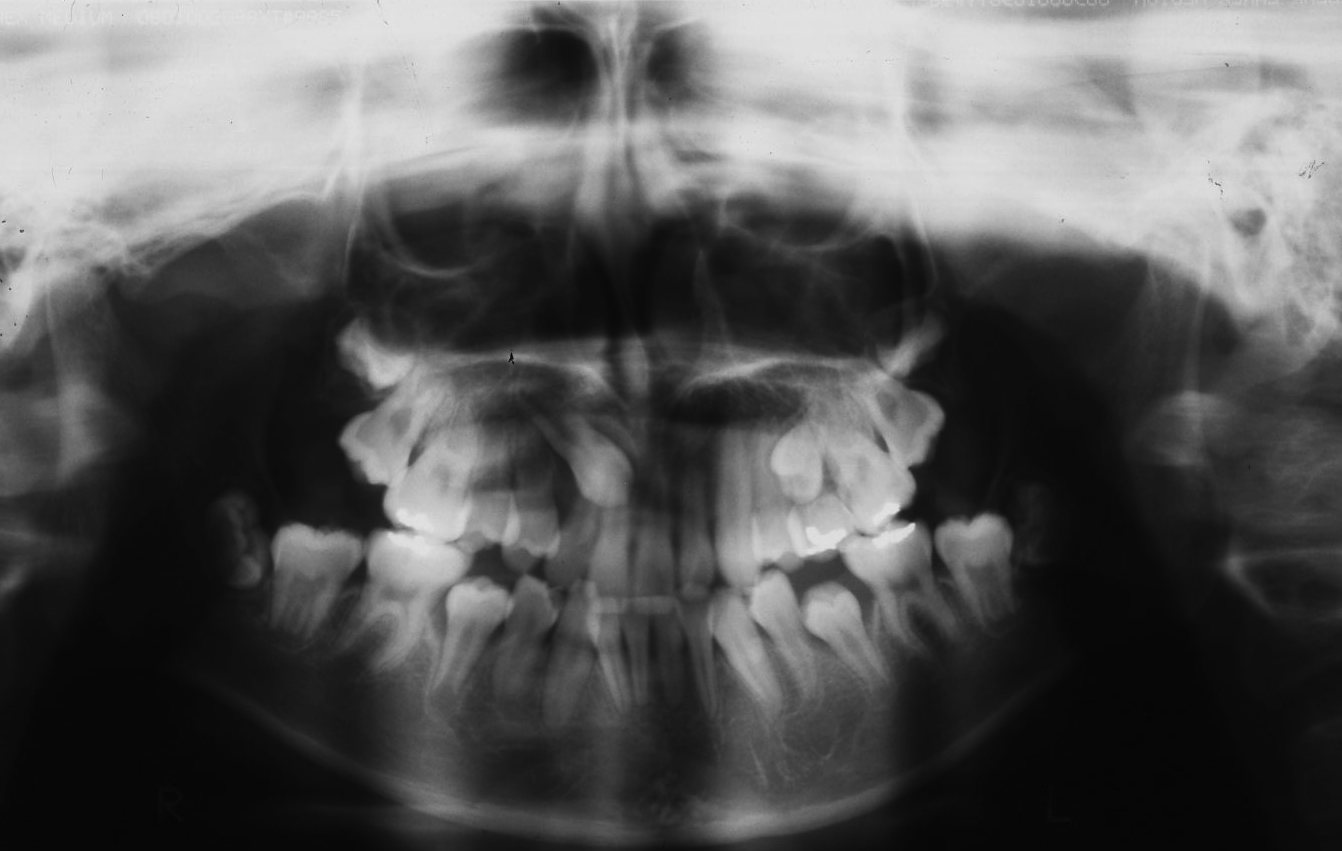

なかなか抜けない歯 その他 歯に関する相談 Ask Dentist11ヶ月前にケガにより左1の歯が抜けました。 その後、左2の歯が少しずつ、抜けた なかなか抜けない乳歯への対処法 私たちの歯は、大人の歯である「永久歯」と子どもの歯である「乳歯」の2つに分けることができます。 いずれも生えてくる順番や時期というのは大体決まっています。 とくに乳歯に関しては抜け落ちる時期にも順序が昨日下の乳歯が抜けないのであおば歯科クリニックに来院した女の子のケースをご紹介します。 左下の乳歯がぐらぐらしているのですが、なかなか抜けてくれないそうです。 内側から永久歯が顔を出しています。 抜歯することをお勧めして、抜歯しました。

乳歯が抜けずに永久歯が生えてきた場合、 その乳歯がすぐに抜けそうかどうかで、治療方針を決定します。 抜けそうなぐらい乳歯がぐらぐらしている場合は、 自然に抜けるのを待っても問題ありません。 一方、乳歯が抜けそうにない場合は、 乳歯がグラグラなのになかなか抜けない! って時はこうしよう 息子の幼稚園もあとわずか。 小学校入学が迫ってきて、楽しみなのと同時に幼稚園ももう卒園かと思うとなんとなく寂しいような気もしますね~w このくらいの歳になると歯が抜けたという大人乳歯の人は乳歯が抜けないように2つのことに気をつける 大人乳歯の人は、乳歯が抜けてしまうと、もう次の歯は生えてきませんので、抜けないように以下の2つのことに気を付けなければいけません。 虫歯や歯周病などの歯の病気 乳歯そのものの